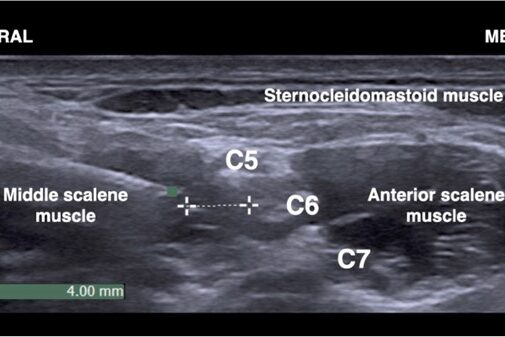

POCUS NEL CONTESTO PREOPERATORIO – CUORE Fabio Magarotto1, Federica Arturi1, Gabriele Melegari2 Università degli Studi di Modena e Reggio Emilia, Scuola di Specializzazione Anestesia e Rianimazione, Terapia Intensiva e del…